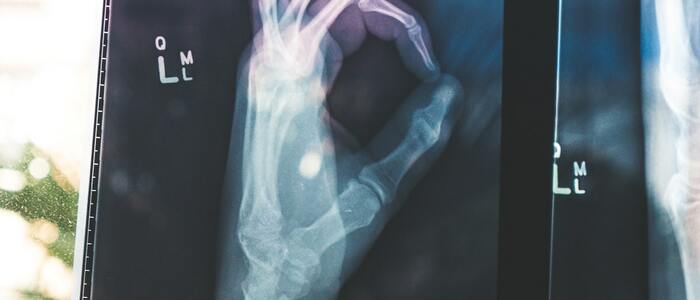

Osteoporóza je nemoc kostní tkáně. Vede ke značně zvýšené křehkosti kostí a tak jsme více náchylní ke zlomeninám. Toto onemocnění postihuje ve větší míře ženy, a především v období klimakteria, kdy dochází k většímu vyplavování minerálů a úbytku kostní hmoty.